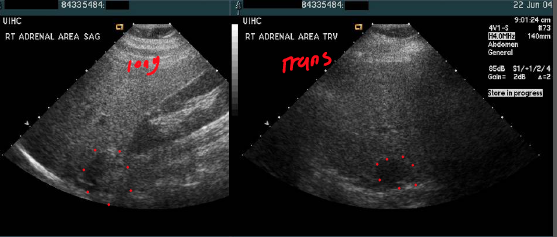

what is demonatrated here?

adenoma (notice how round the gland is)